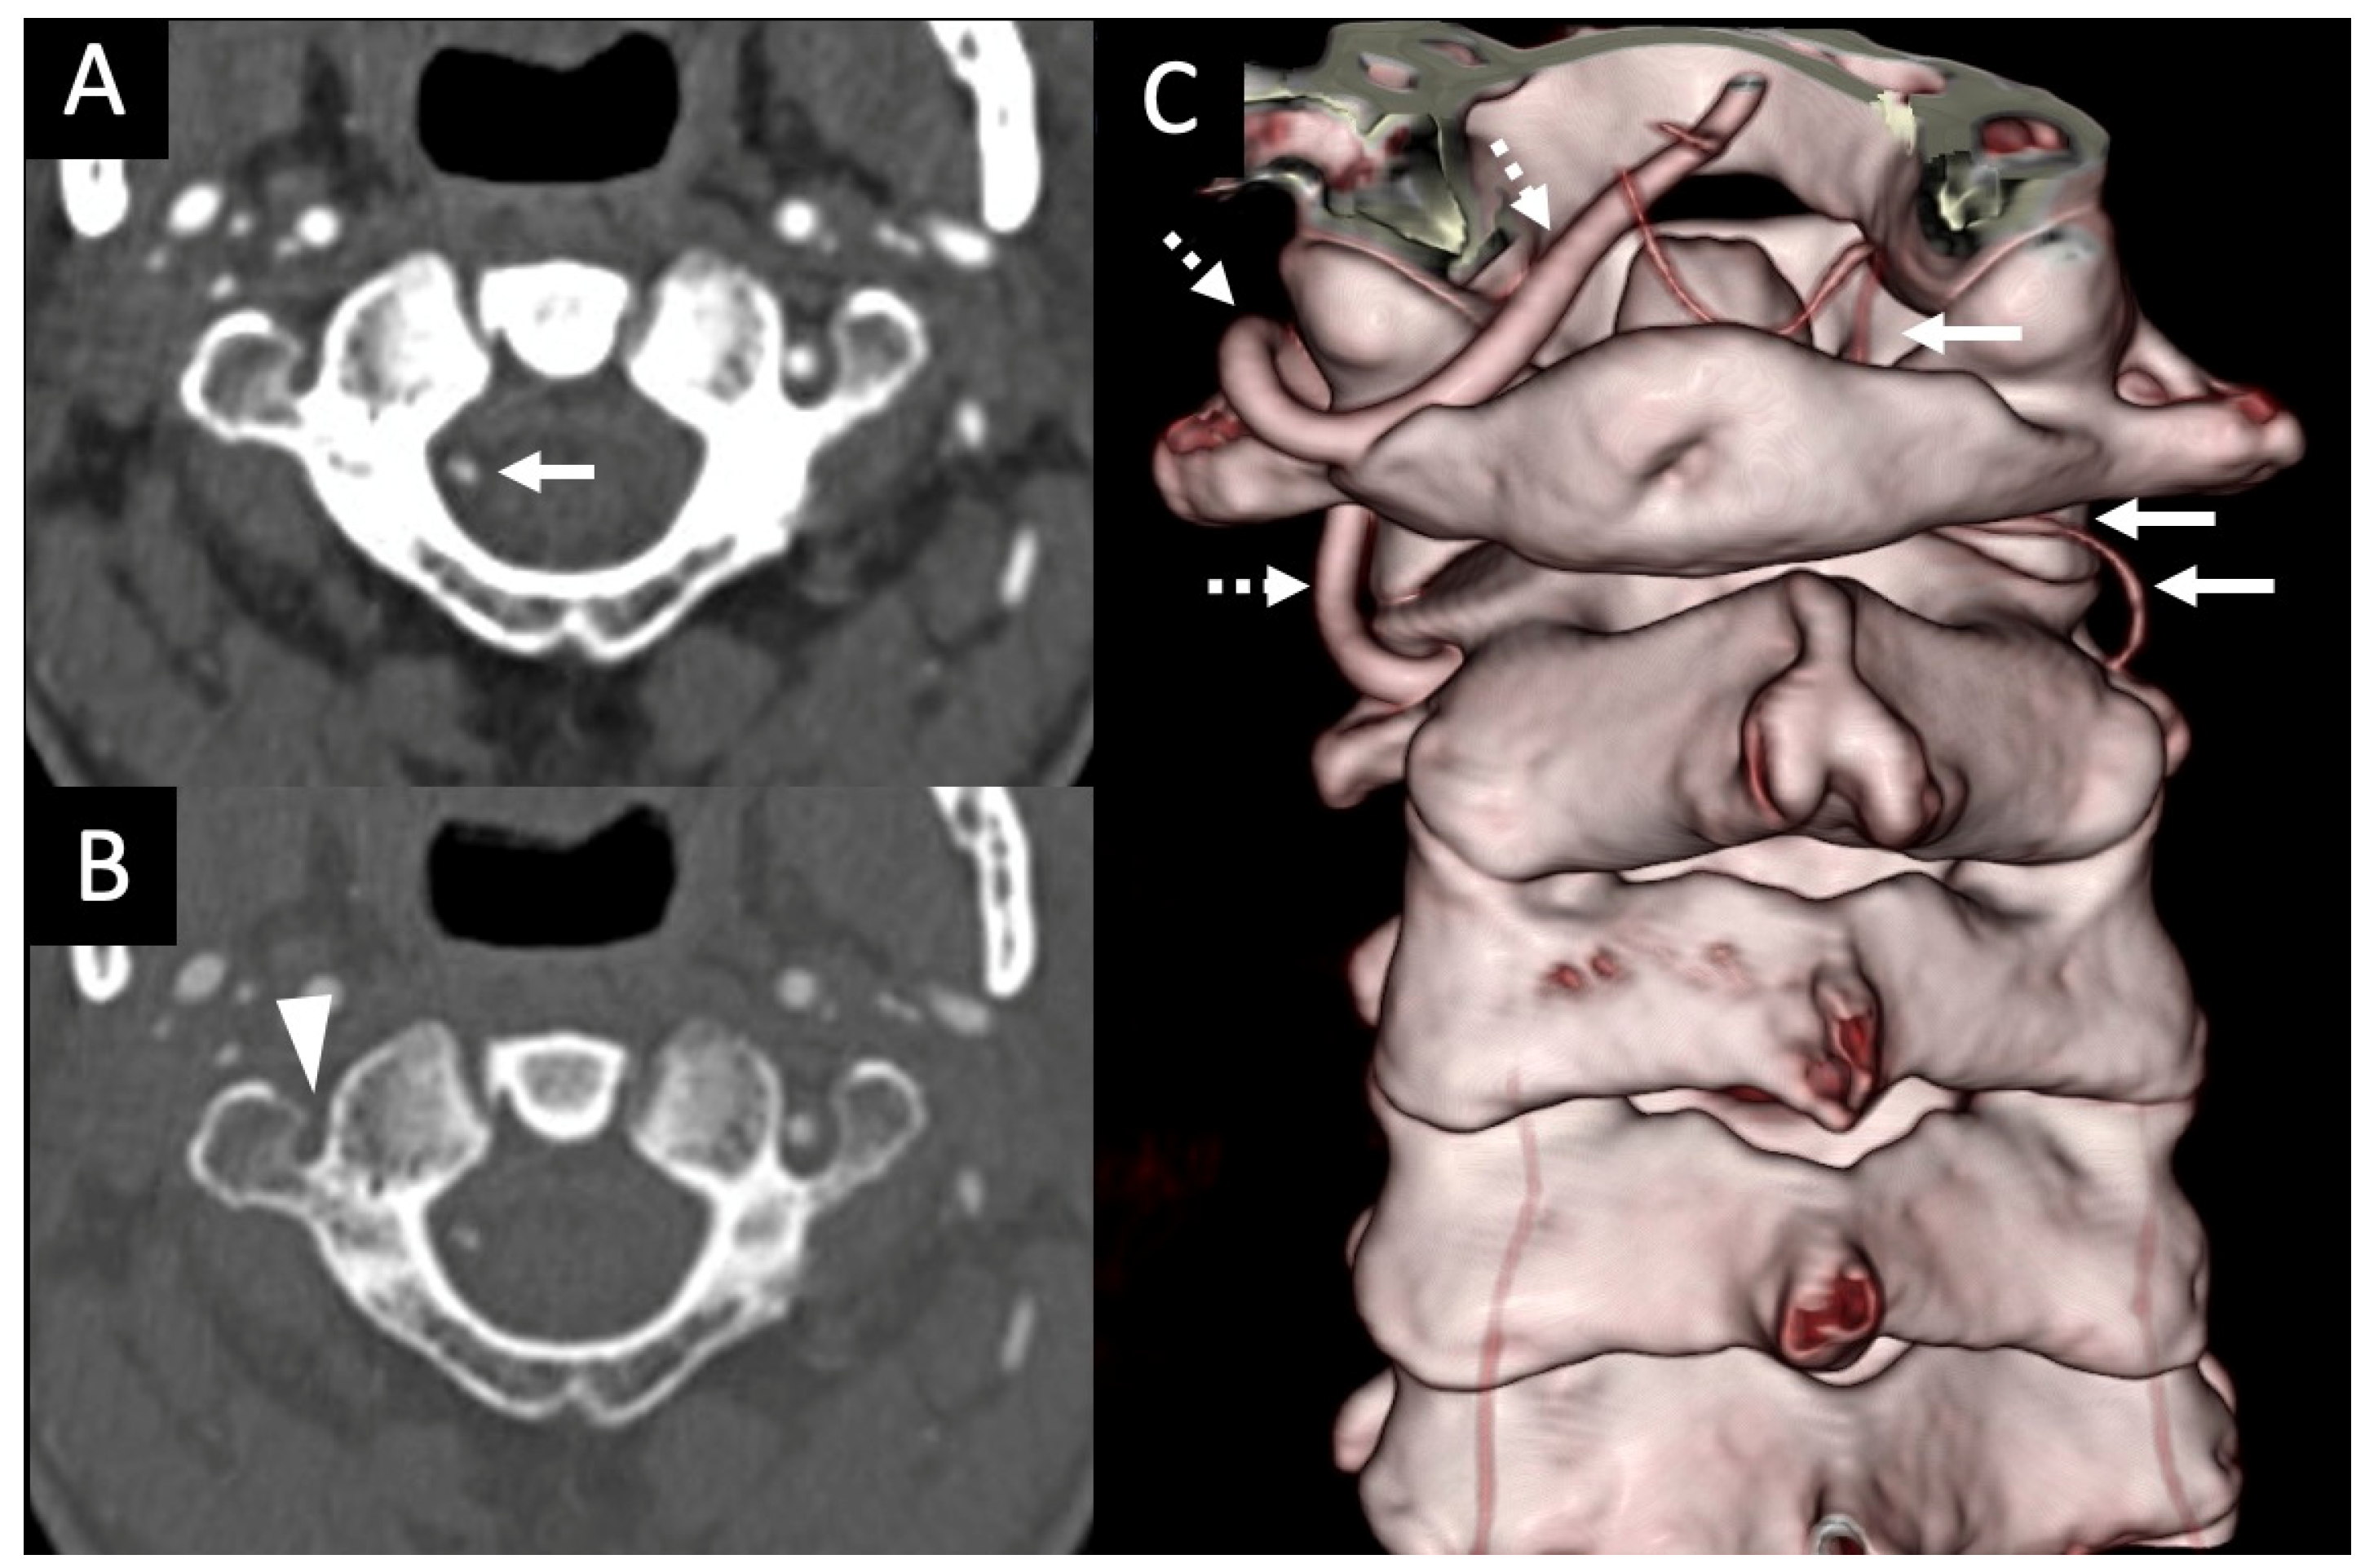

3.1. Variations in the V2 Segment